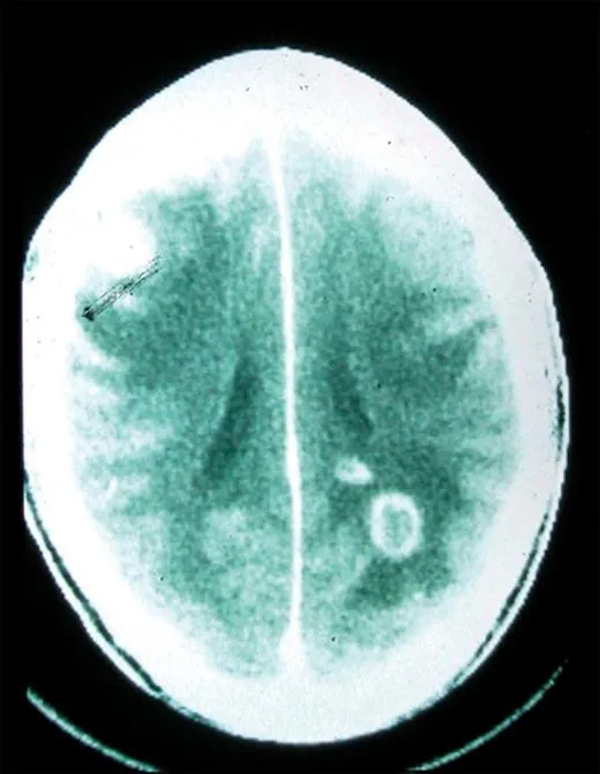

弓形虫感染人类大脑(图片来源:Sullivan & Jeffers, 2012)